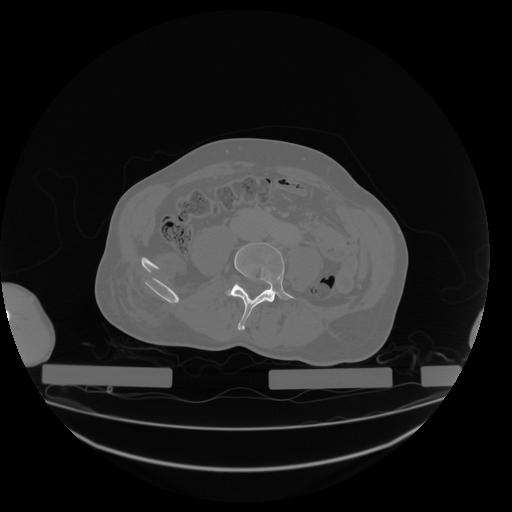

34 CUERPO,CE,Vol,1.0,CUERPO,,